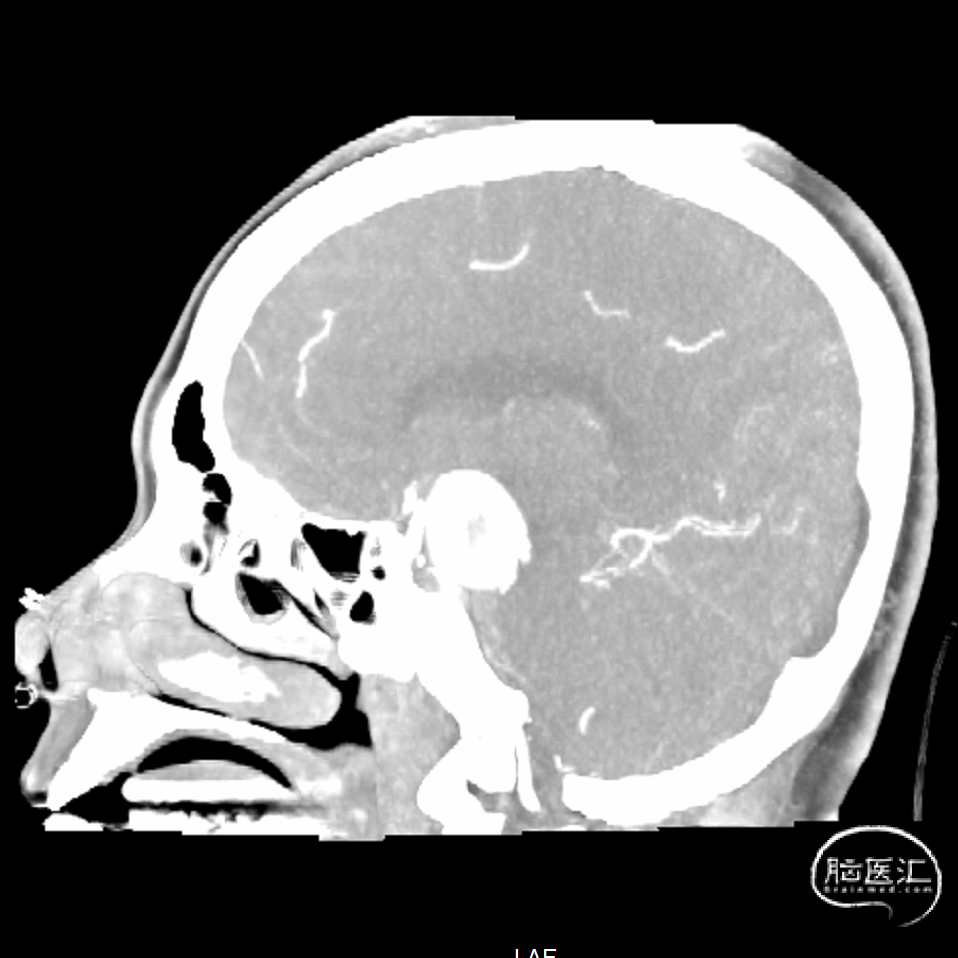

我院头颅CT+CTA检查提示:蛛网膜下腔出血,左颈内动脉交通段边缘突起伴不均匀强化,动脉瘤首先考虑。

CTA